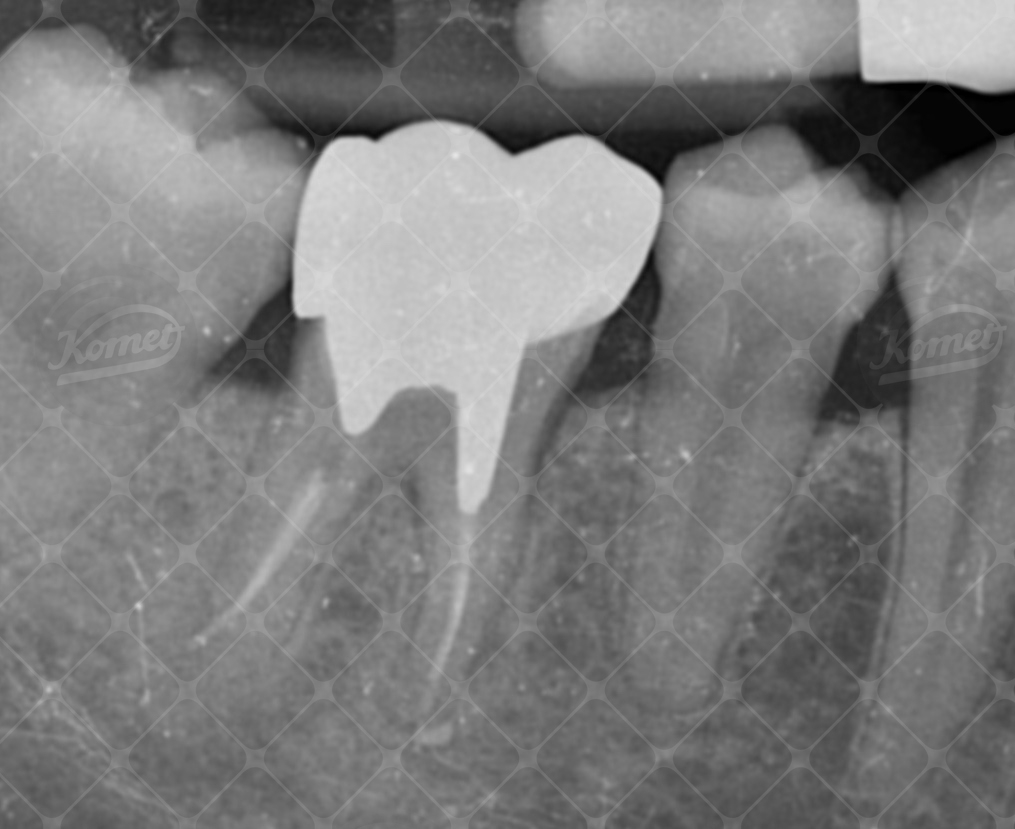

La radiografia finale endorale (Fig 13) mostra la stabilità dei livelli ossei marginali, con una adeguata distanza tra la cresta ossea ed il margina di chiusura protesico.